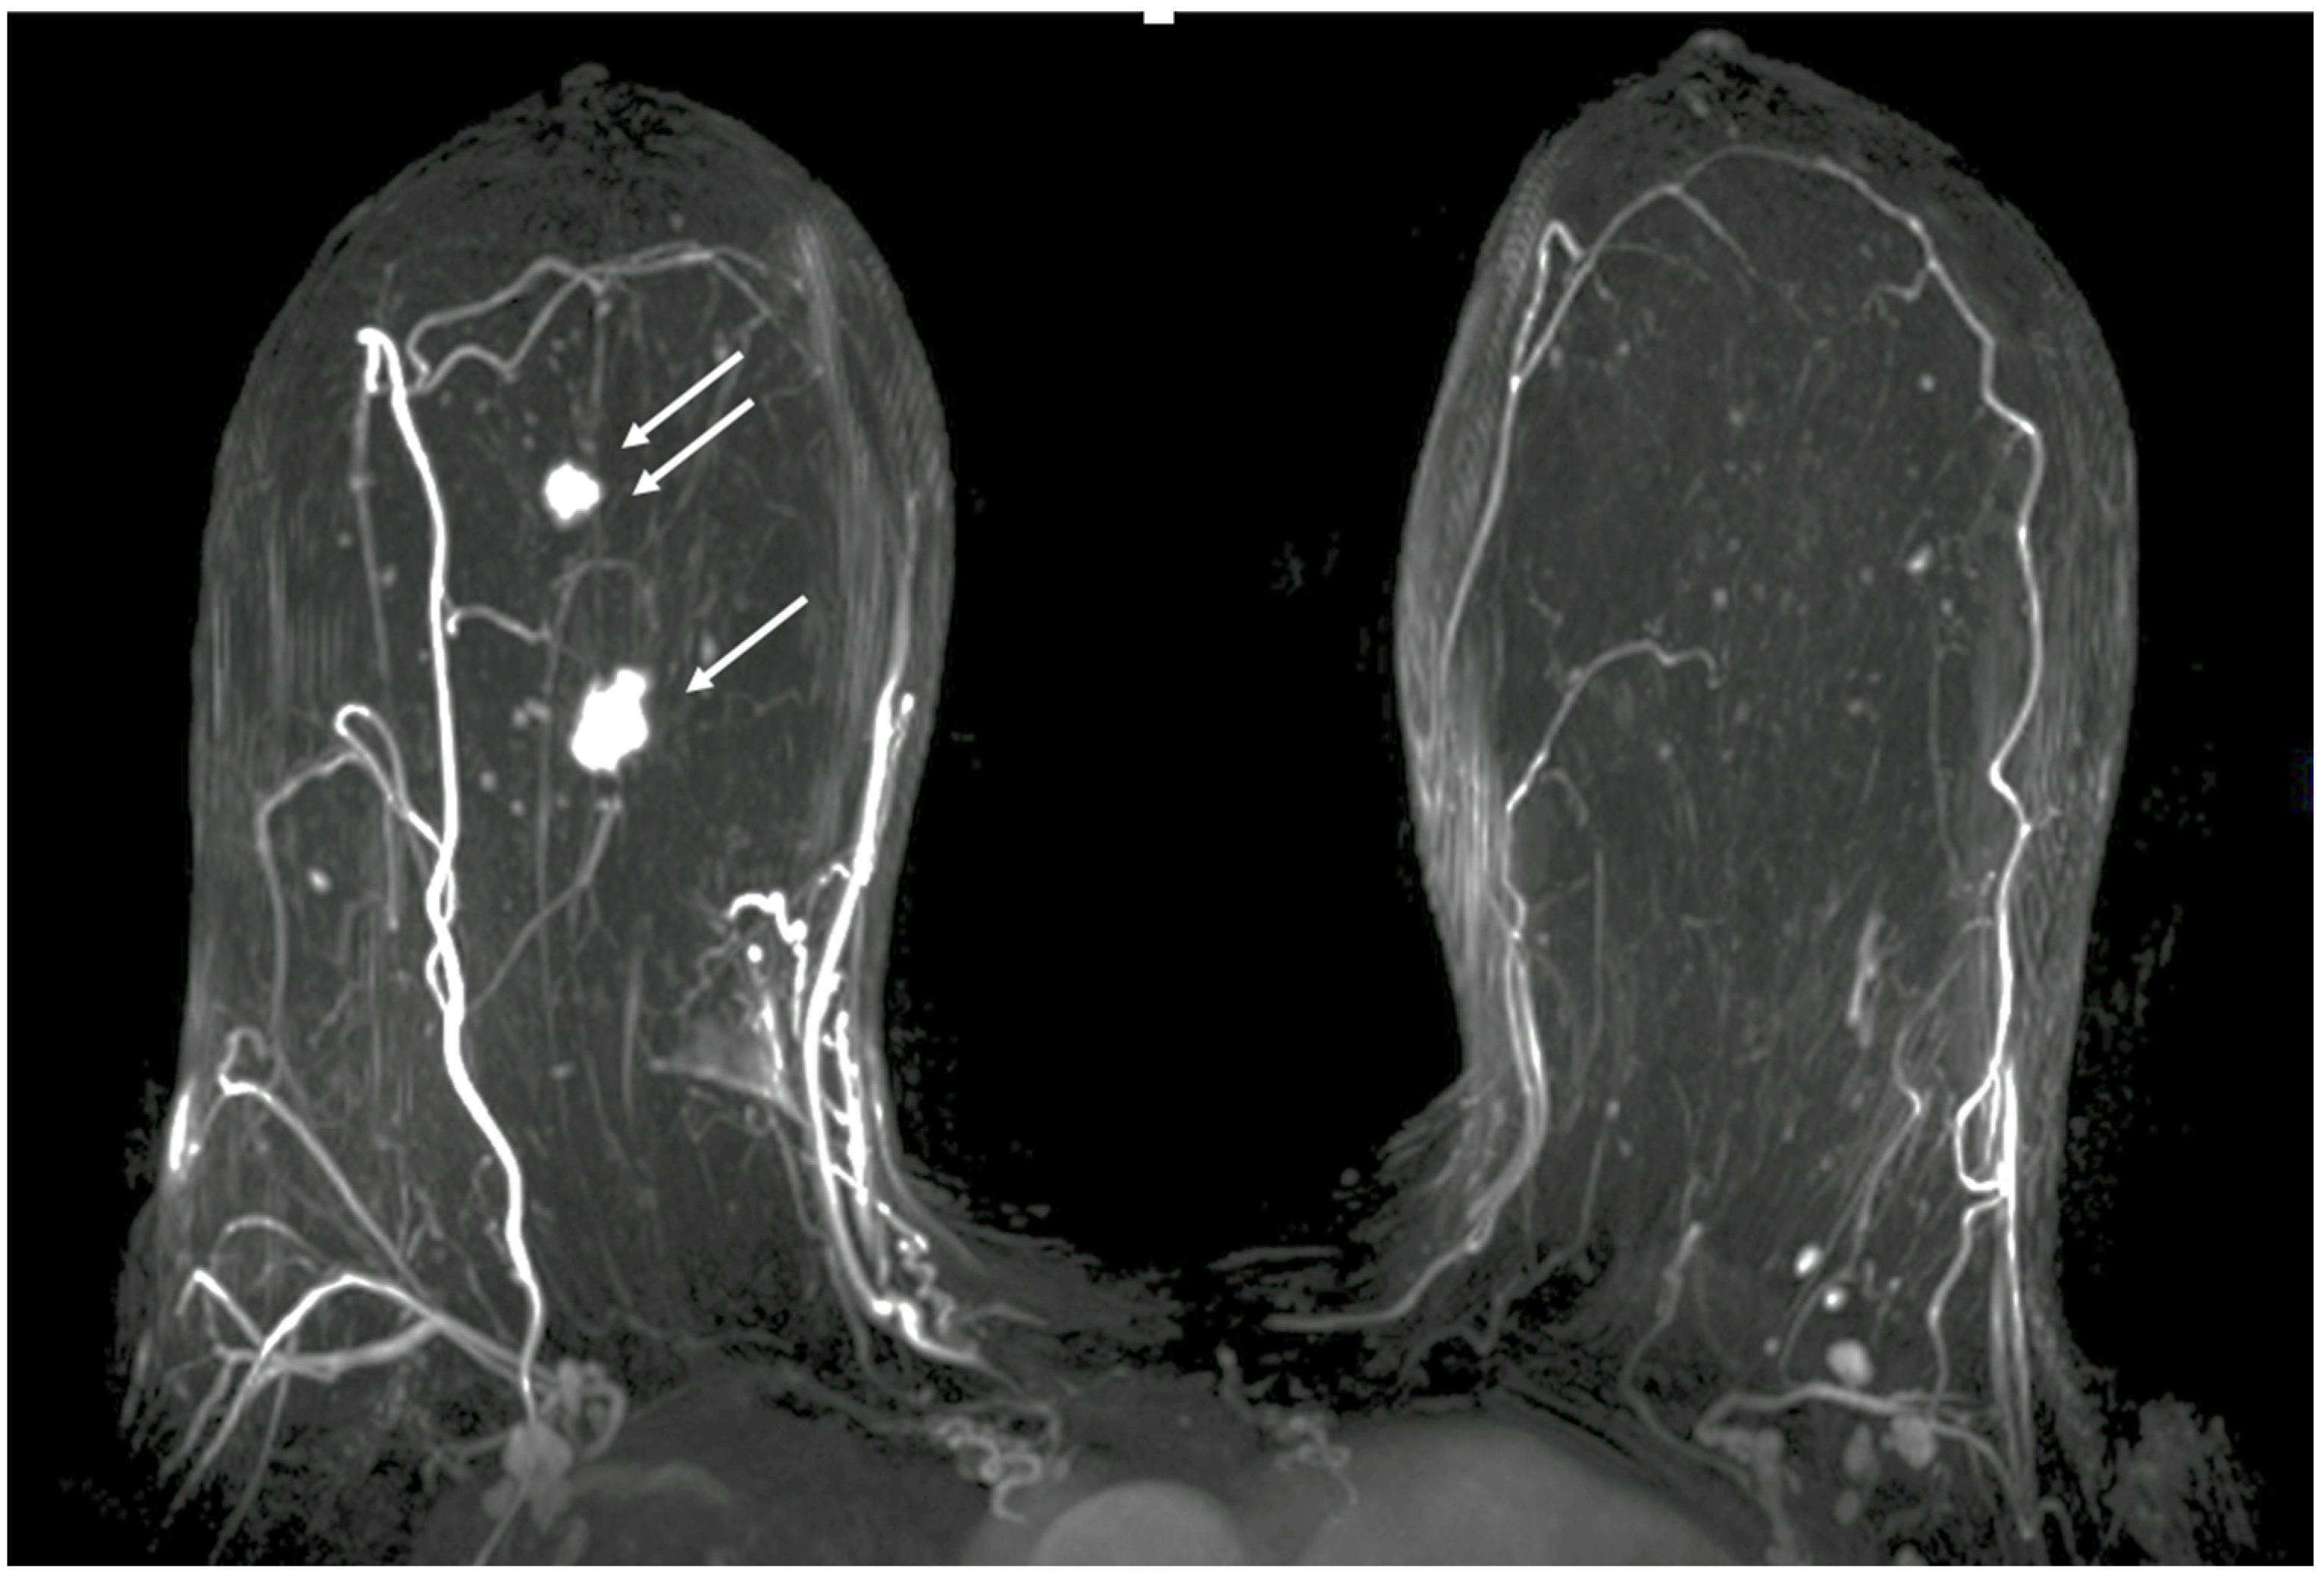

Contrast-Enhanced Breast MRI. Contrast enhanced breast MRI improves assessment of disease extent, including detection of spiculations, multifocal, multicentric, or contralateral disease, which might impact eligibility for cryoablation or alter the overall treatment plan (Figure 4). Contrast-enhanced breast MRI has the added value of permitting 3-D image reconstruction to permit viewing of the tumor from various angles for a more comprehensive assessment of tumor shape and size. Breast MRI for cancer evaluation requires the use of an intravenous contrast containing gadolinium that can be safely administered with minimal short-term and long-term risks. However, patients unwilling or unable to receive gadolinium might be able to access dedicated breast-only diffusion weighted MRI, which has limited availability in the U.S.

Figure 4.

Contrast-enhanced breast MRI image showing multifocal disease indicated by mass-like enhancement of dominant mass (indicated by single arrow and encircled with hash marks) as well as mass-like enhancement of a second focus of disease (indicated by double arrows and encircled with hash marks). The second focus was mammographically-occult.